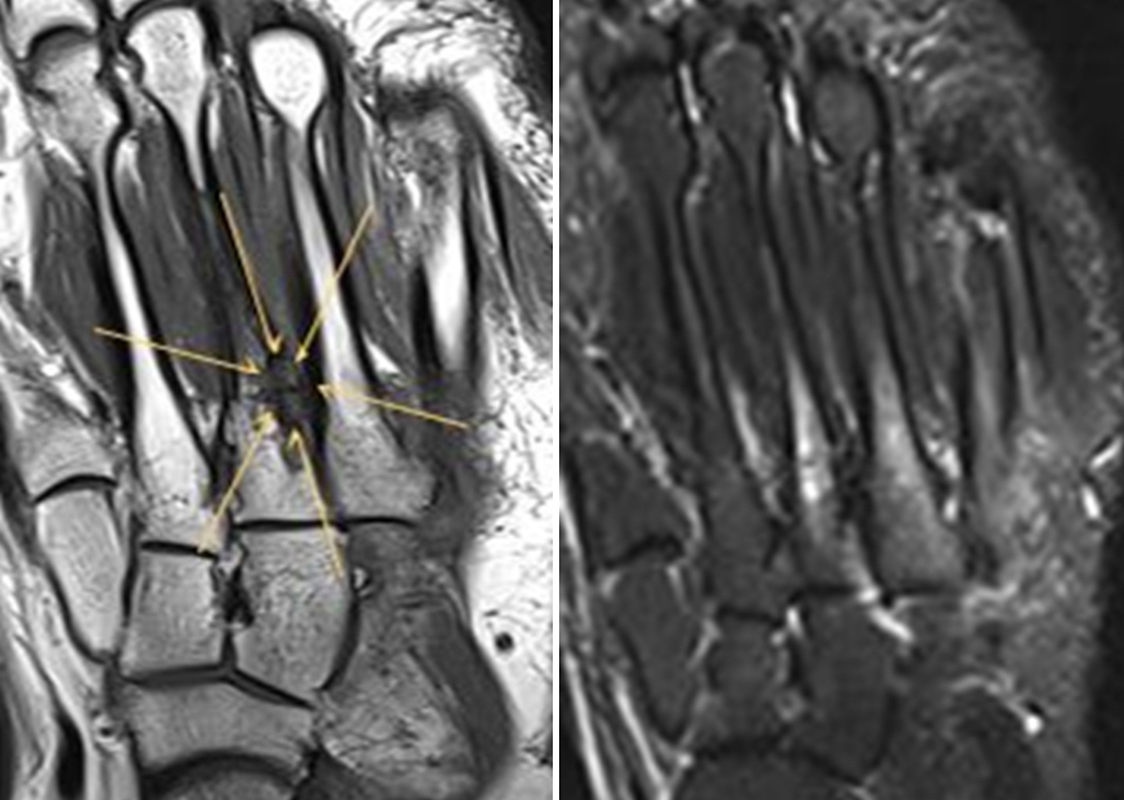

Abbildung 2.1.

Bildbeispiele symptomatische OCL

Zum Lesen der Bildbeschreibung und zur Vollansicht bitte das Bild anklicken. Bild: H. C. Rischke

Abbildung 2.2.

Bilder eines Patienten mit Z. n. mehrfachen Sprunggelenksdistorsionen in der Vergangenheit, besonders heftige Distorsion des linken Sprunggelenkes 5 Wochen vor der Untersuchung. Die SPECT/CT zeigt eine instabile osteochondrale Läsion mit deutlicher Aktivierung.

Abbildung 2.3.

Klärung bei Schmerzen im rechten OSG bei OCL an der medialen Talusschulter. Z. n. OSG-Distorsion vor 2 Jahren und Z. n. OSG-Fraktur / Syndesomosenruptur. Ausgedehnte OCL, hier jedoch kein erhöhter Knochenmetabolismus; lediglich Nachweis einer Stressreaktion im Bereich der Synchondrose eines Os trigonum als Schmerzursache.